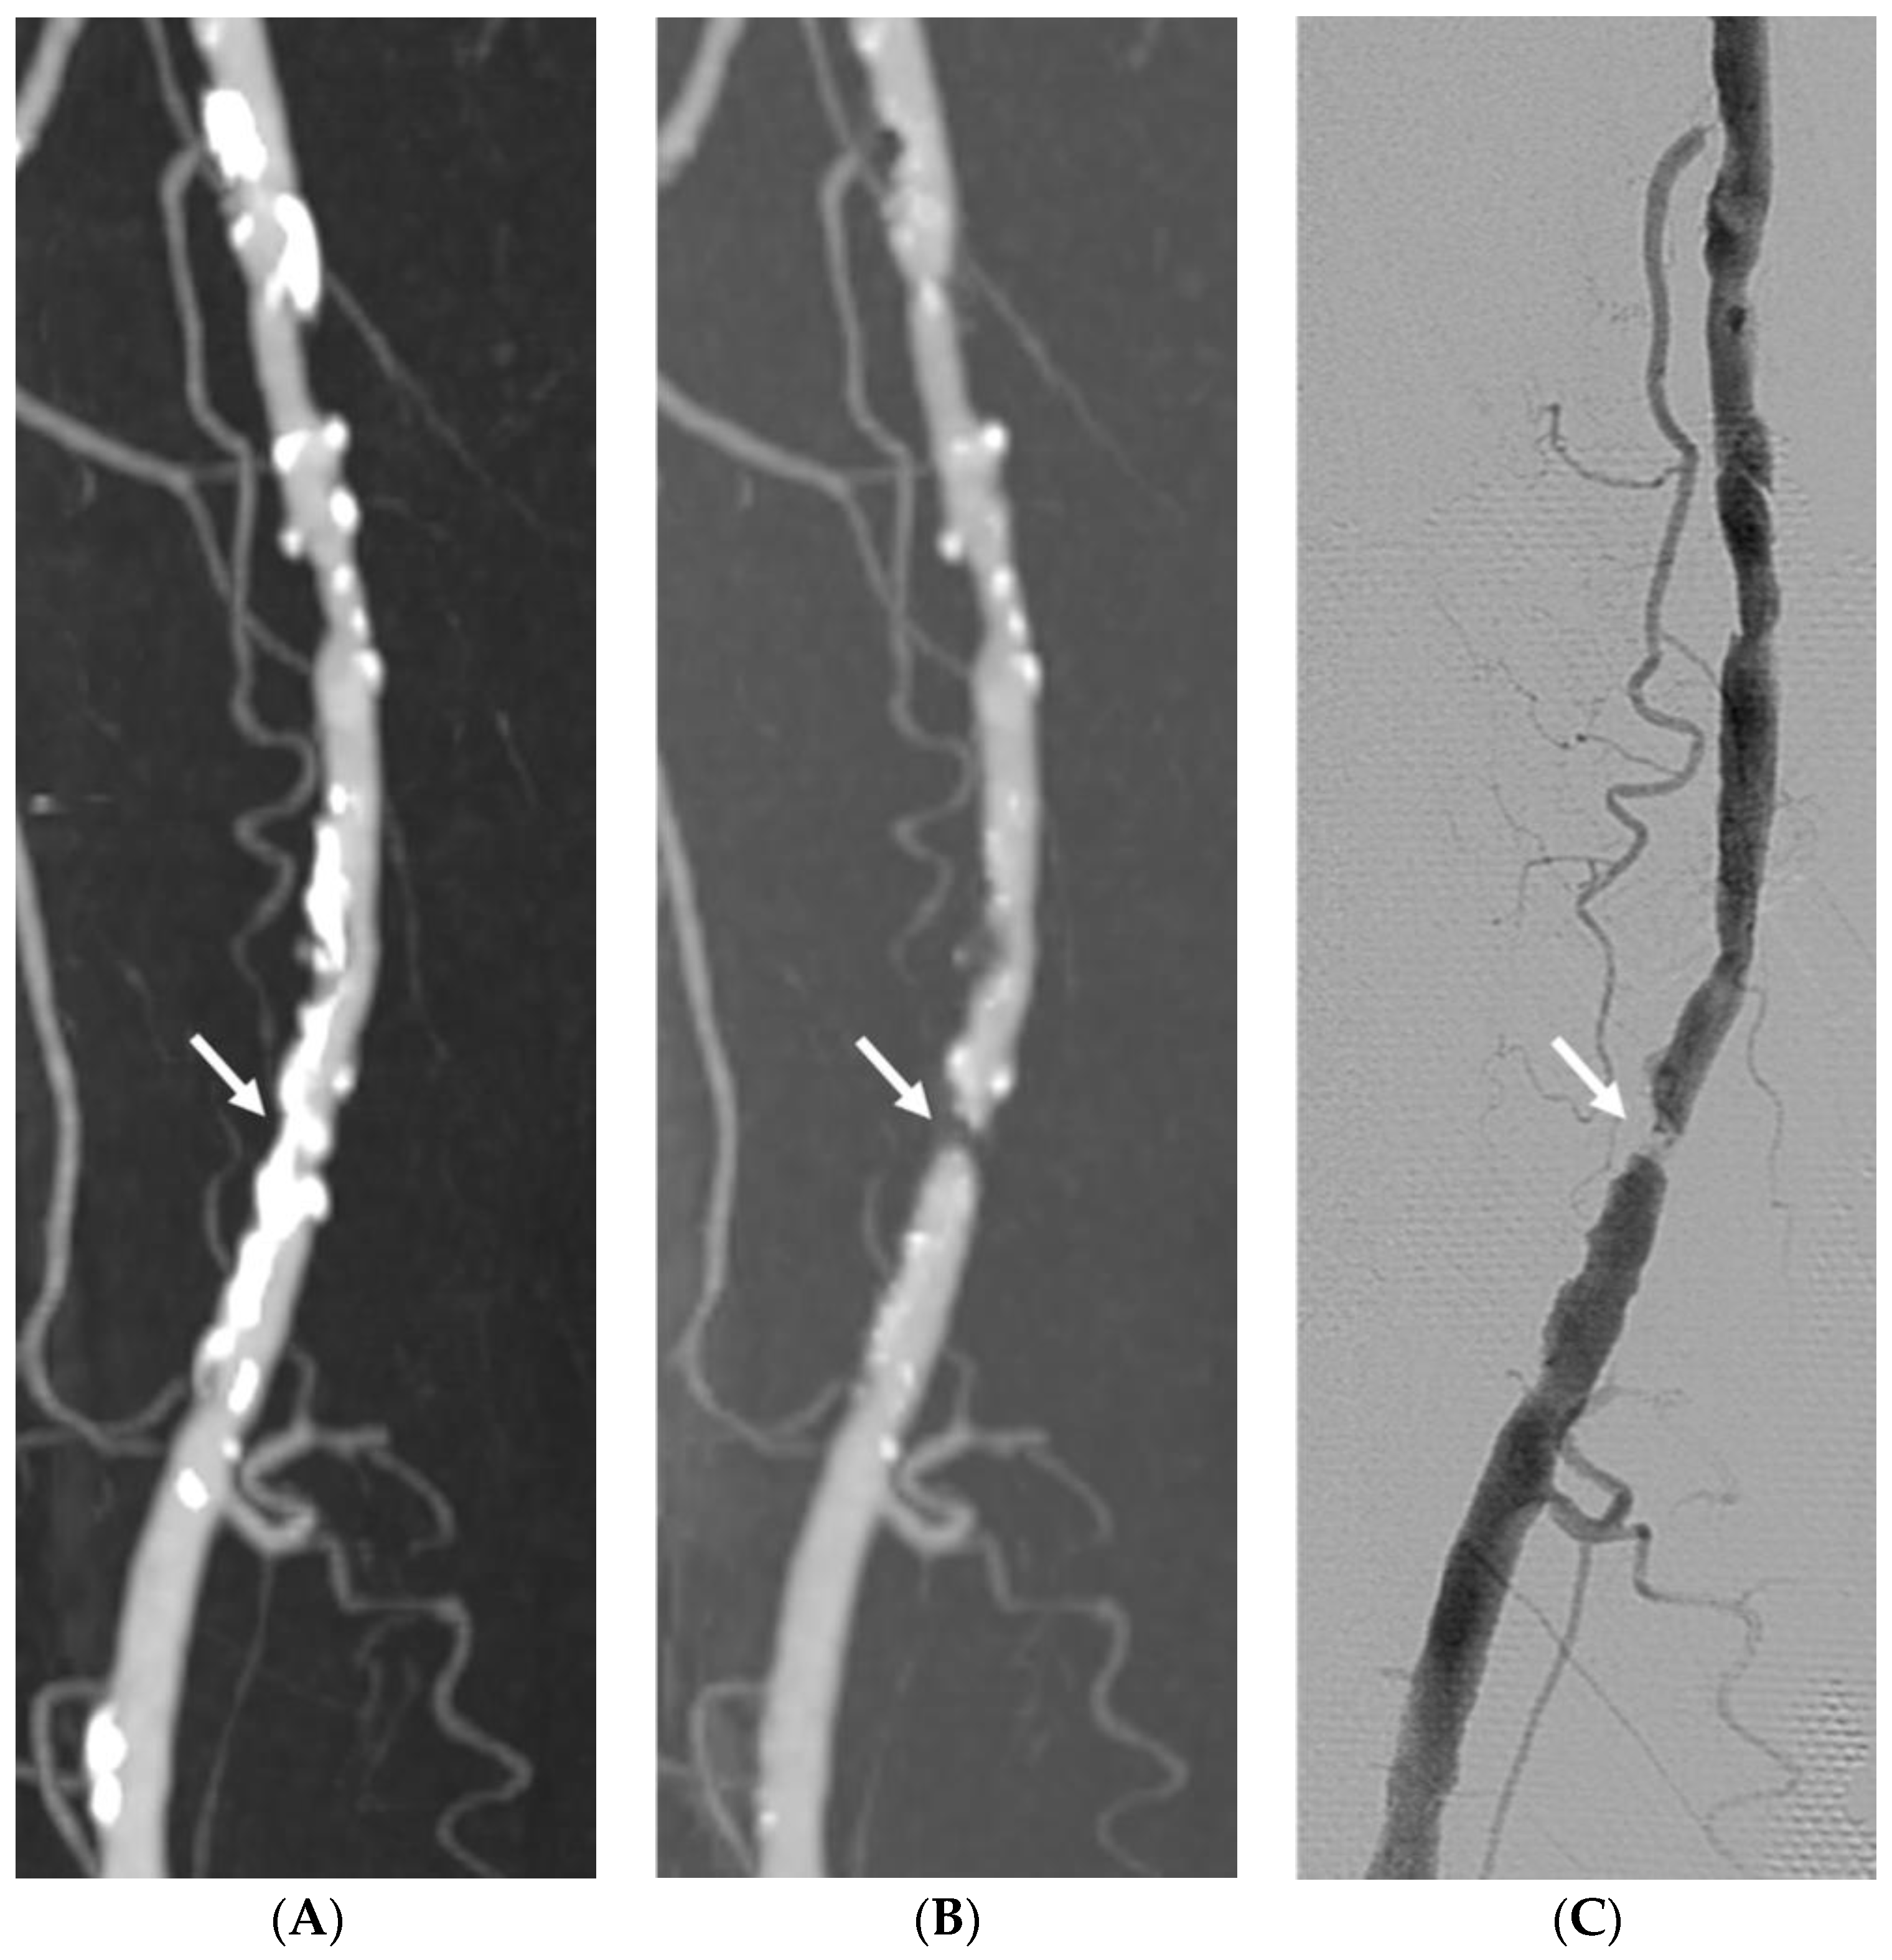

3.1. Image Quality

3.2. Diagnostic Performance

3.3. Impact of Vascular Wall Calcification